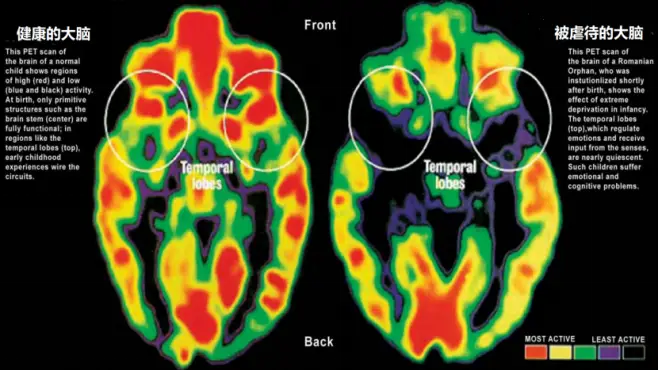

玩手机的大脑_在孩子脑袋上玩手机_孩子玩手机游戏很投入大脑

你说,他们的大脑这时候在干啥呢?我猜啊,肯定是在经历一场超级大脑风暴!那些色彩斑斓的画面,那些紧张刺激的关卡,每一秒都在刺激着他们的小脑袋瓜。他们的注意力高度集中,反应速度也跟着飙升,这感觉,就像是大脑在开派对,热闹非凡!